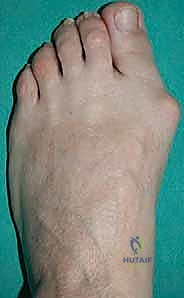

هل تعاني من ألم مستمر في قاعدة إصبع قدمك الكبير؟ هل تلاحظ وجود نتوء عظمي بارز يسبب لك الإزعاج الدائم، ويجعل من مهمة اختيار وارتداء الأحذية كابوساً يومياً؟ قد تكون مصابًا بحالة طبية شائعة ومزعجة تُعرف باسم "إبهام القدم الأروح" (Hallux Valgus) أو ما يُطلق عليه شعبياً "الوكعة" (Bunion). هذه الحالة لا تتوقف عند كونها مشكلة تجميلية فحسب، بل هي تشوه هيكلي يؤثر بشكل عميق ومباشر على جودة الحياة، القدرة على ممارسة الرياضة، وحتى المشي لمسافات قصيرة.

إبهام القدم الأروح ليس مجرد "عظمة زائدة" أو نتوء عظمي بسيط ينمو فجأة كما يعتقد الكثيرون. بل هو في الواقع تشوه ميكانيكي معقد ومتطور يصيب القدم الأمامية. يتميز هذا التشوه بانحراف تدريجي ومستمر لإصبع القدم الكبير نحو الأصابع الأخرى (نحو الجانب الوحشي للقدم)، مما يؤدي بالتبعية إلى بروز رأس عظمة المشط الأول في الاتجاه المعاكس (الجانب الإنسي للقدم)، مكوناً ما نراه ونشعر به على أنه "نتوء عظمي".

- بروز عظمي مرئي: نتوء واضح عند قاعدة إصبع القدم الكبير.